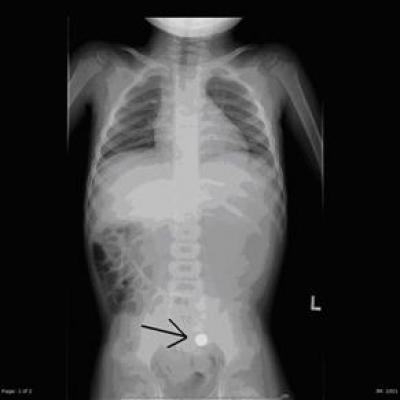

Ornament-related injuries often lead to otherwise avoidable medical procedures. Facial lacerations have required stitches. In addition, accidental ingestions have required testing with X-rays and CT scans, and there is particular concern of radiation exposure from CT scans in children. Such hospital visits are also an unwelcome inconvenience during the holiday festivities, Lee says.